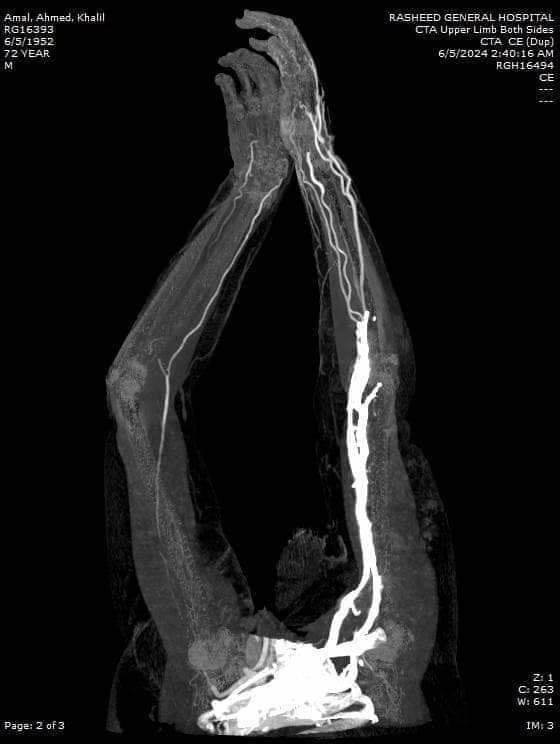

نجح الفريق الطبي بمستشفى رشيد المركزى للمرة الثالثة في اجراء عملية جراحية متقدمة حيث قام الفريق الطبي بقسم الجراحة بإجراء عملية جراحية لتسليك شريان ذراع أحد السيدات واستئصال الجلطات من الذراع الأيمن لمريضة بالعناية المركزه وتم إنقاذ الذراع من البتر ، والمريضه في قسم العناية المركزة بحالة مستقرة .

وقام بإجراء العملية الجراحية بنجاح أعضاء الفريق الطبي الآتى أسماؤهم "الدكتور منير الفخراني استشاري الأوعية الدموية، الدكتور محمد المحلي أخصائي الجراحة، الدكتور السيد عمران أخصائي التخدير ، والدكتور محمد زاهر أخصائي العناية المركزة ونائب مدير المستشفى ، الدكتور أحمد الترمسى رئيس قسم العناية ، ومشرفات تمريض قسم الجراحة والعمليات ، والعناية المركزة ، وقسم الأشعة .